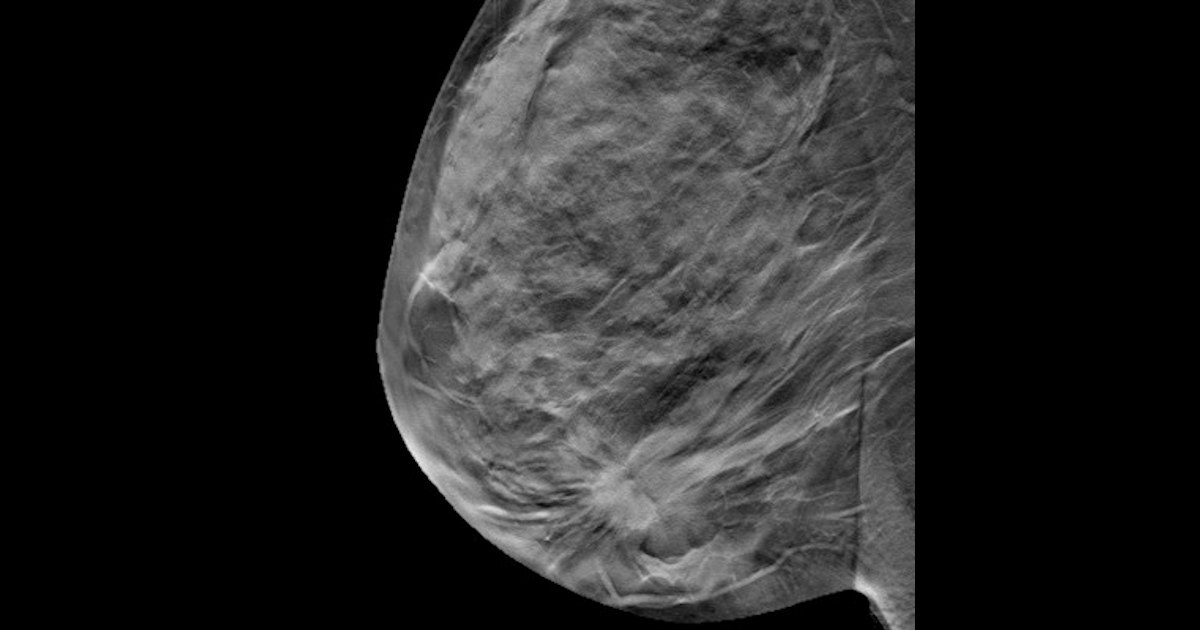

Surveillance mammography is common practice for imaging women who have already been treated for breast cancer since they are at an elevated risk of developing a second breast cancer.

For elderly women with a personal history of breast cancer, critics say that ongoing surveillance imaging may lead to overdiagnosis and overtreatment of cancers that may not be harmful if left untreated due to competing mortality risks based on age or comorbidities.

Berger and colleagues wanted to characterize current mammography patterns for elderly women with a personal history of breast cancer, taking life expectancy into consideration.